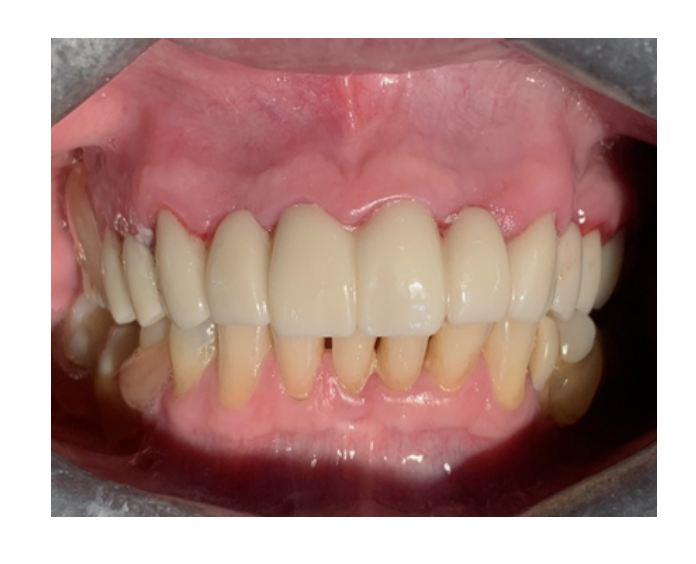

Prótesis fija de zirconia

sin metal